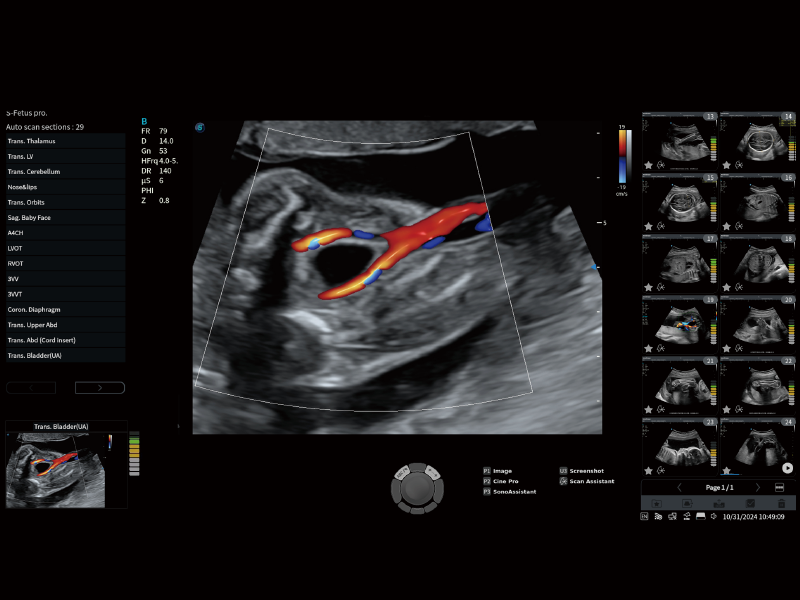

丰富的血流动力学检测技术,可在不同医疗场景中高效捕捉血流信号,助力临床诊疗。

在传统血流的基础上优化扫查和算法策略,能够更好的抑制组织信息,提炼红细胞运动信息,得到更高帧频,高灵敏度和分辨率的血流信号,还原更真实的血流动力学。